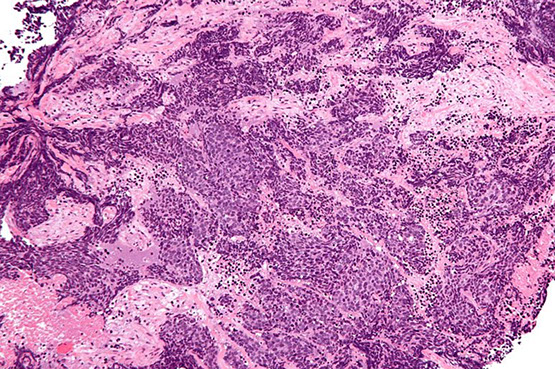

Nasopharyngeal ca

Nasopharyngeal ca - EBER

Nasoparyneal Carcinoma

- subtypes: keratinizing (1/4), nonkeratinizing (1/7) or undifferentiated (3/5)

- ~1/5 cancers in China

- inc EBV titers in non-K and undiff types, no clear causal relation

- different growth patterns: Rigaud (cohesive) vs Schminke (discohesive)

Keratizing: looks like any other SCC

Nonkeratinizing (undifferentiating) subtype

- common in SE Asia and parts of Asia, younger pts usually; sometimes presenting as a neck mass

- no K, syncytial groups of large cells c pale chromatin and mprominent nucleoli, inc lymphs, no desmoplasia

- genetic and envt factors (1/5 cancers in Hong Kong), assoc c A2/sin HLA profile in chinese

- EBV assoc

- asymptomatic; neck mass

Tx: Rads (high dose) usually done 2/2 stage

- K type not responsive to rads

Px: undifferentiated has the best px (radiosensitive)